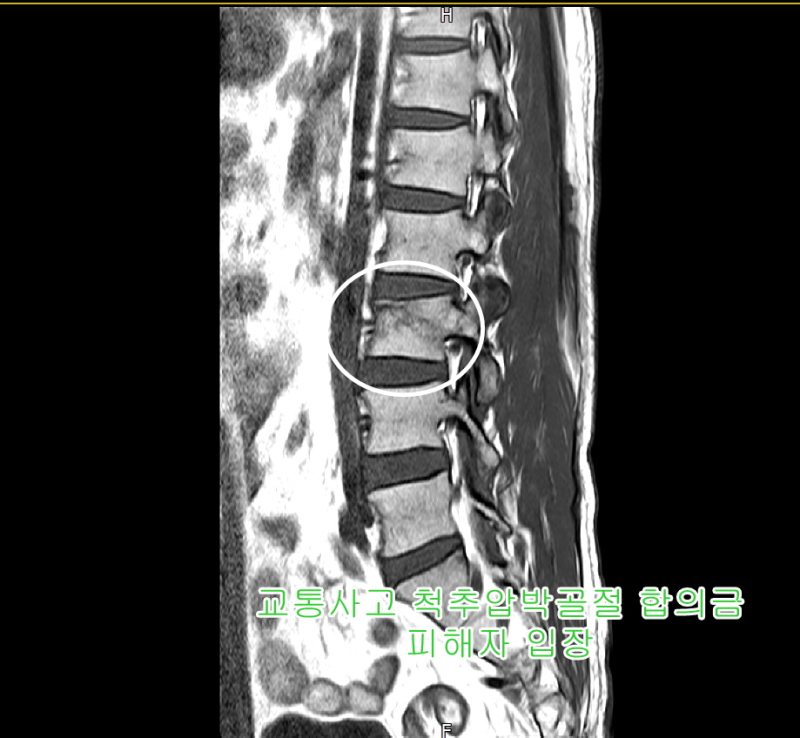

2차 요추골절 오토바이 교통사고 비수술적 치료 3000만원 보상산출 사례

고객은 사고로 인한 요추 2차 골절 진단을 받았고 TLSO 흉요천골 보조기를 착용한 상태에서 침상 안정이 필요했습니다. 12주, 즉 3개월을 쉬어야 했다. 압박골절은 무조건 장애인가요?

문제는 제2요추를 포함한 모든 척추 압박골절이 X-ray로 진단된 것이 처음이 아니기 때문에 MRI를 찍는 경우가 있어 변형이 발생할 수 있으며 압박률이 더 늘어날 수 있습니다. 따라서 척추압박골절 진단을 받았다면 성급하게 합의하기보다는 모든 후유증을 충분히 이해하고 치료를 받는 것이 좋습니다. 정산금액은 어떻게 산정되고 보상되나요? 클레임 당사자의 클레임팀에 연락한 고객님도 사고 초기부터 복잡한 클레임 정산 관계에 대한 압박감 때문에 체계적이고 꼼꼼한 클레임 해결을 바라며 연락을 주셨습니다. 공신력 있는 제3의 병원을 통해 정산금액 산정에 필요한 맥브라이드식 잔존평가 치료를 받았습니다. 고객의 연령, 방치, 소득 및 병력을 고려하여 게시된 장애 진단을 기반으로 위자료 및 폐업 손실을 포함한 손실 이익 계산, 법적 손해액 계산. 물론 보험사에서는 장애 진단에 대한 진료를 평가하여 청구 금액을 크게 줄이려고 하지만 10년 이상의 경험과 손해 청구 실무 지식을 갖춘 손해배상 파트너로서 2차 요추 3천만 원의 청구를 받을 수 있었습니다. 비수술적 교통사고 골절. 따라서 교통사고, 특히 오토바이 사고는 과실이나 장애 판정 등의 요인이 많다. 따라서 사고로 인해 2차 요추골절이 발생했다면 사고 초기부터 체계적인 상담을 받으시기 바랍니다. 이것은 무료 상담이며 상담료에 대해 걱정할 필요가 없습니다. 상담방법 1. 전화상담 1688-4951 2. 카톡상담 bosang114 업무상 재해 노무/손해 산정 보상 면제, 업무상 재해 보상 미지급 pf.kakao.com 척추 압박골절 유사사례 찾기 교통사고조정과 장애보험 보상성공 내가 믿고 맡길 수 있는 회사는? 교통사고 손해배상청구 성공사례 및 손해보험 상해보험 청구안녕하세요… blog.naver.com 버스 요추사고 보상 No. 안녕하세요 여러분 보상파트너입니다. 김 @@… blog.naver.com 독립 교통사고 손해사정사, 발목 골절 수술 보상팀장. 안녕하세요. 보상 파트너 손해 팀. 이 글을 찾는 대부분의 사람들은 교통사고를 당해 피해가 누구인지 알고 있습니다. blog.naver.com